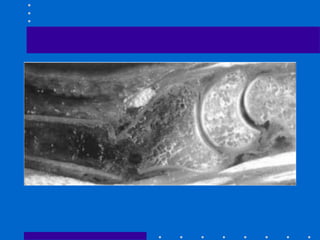

Anatomia Óssea

• NO AP: osso mais forte subjacente à faceta

lunar do rádio

• Inserção dos ligamentos R-U distais

palmares e para o lig radiolunar mais forte

• Deslocamento deste fragmento leva a

restrição da rotação e deslocamento palmar

do carpo

• Figura 26-10